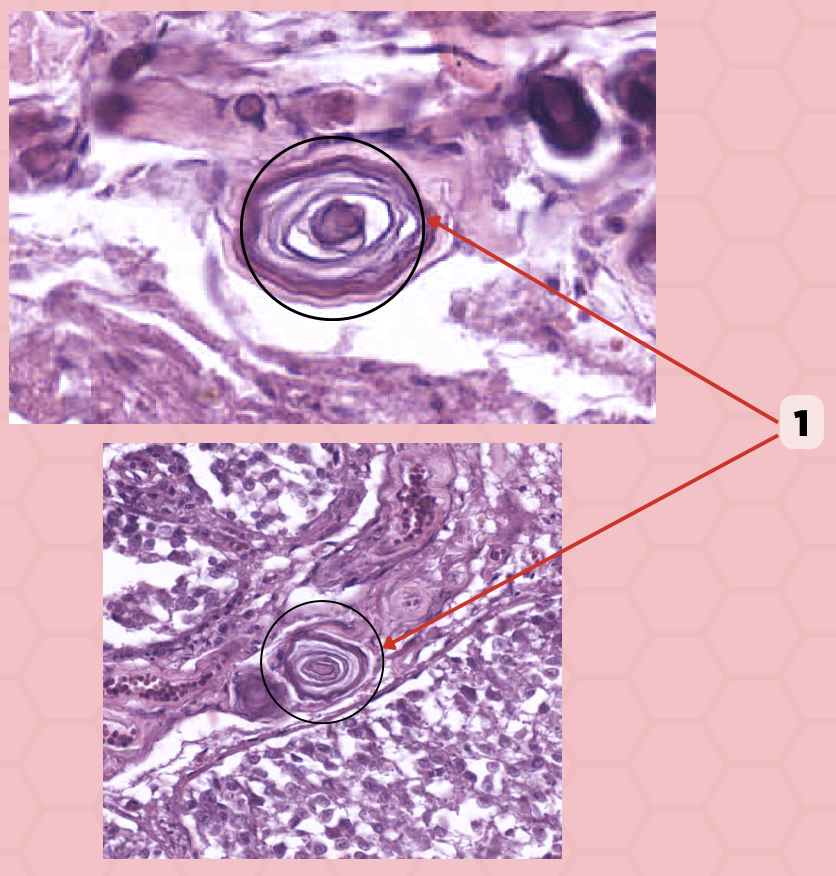

Thyroid-Parathyroid

Identify the specimen.

Thyroid Gland

Identify the structure labeled as 1.

Capsule

Identify the structure labeled as 2 and 4.

Parathyroid Gland

Identify the structure labeled as 3.

Thyroid

Identify the specimen.

Lobules

Identify the structure labeled as 1.

Follicles

Identify the structure labeled as 2.